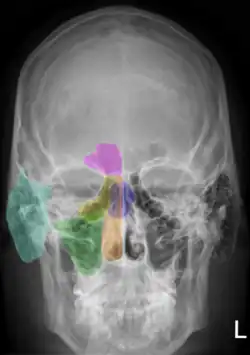

Nasenhöhle und Nasennebenhöhlen des Menschen im Röntgenbild des Menschen auf einer Seite farbig unterlegt.

orange: Cavum nasi

grün: Sinus maxillaris

gelb: Cellulae ethmoidales

lila: Sinus frontalis

blau: Sinus sphenoidalis

zyan: Processus mastoideus